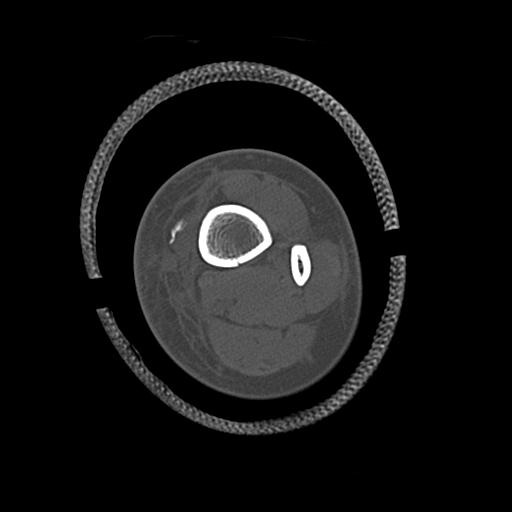

102803 1/12(キウスなし) 1/27 左下腿 4R 30歳女性 左脛骨軸内釘